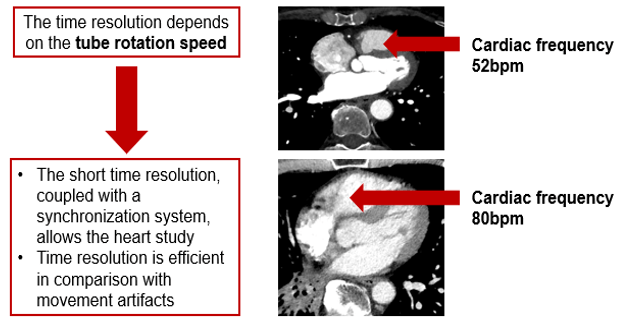

Temporal Resolution

Temporal resolution is an indication of a CT system’s ability to freeze motions of the scanned object. Several factors influence the temporal resolution. The key factors are the gantry rotation time, acquisition mode, type of image reconstruction, and the pitch.

The concept of temporal resolution is fundamental to cardiac CT and MRI, in which a rapidly beating heart is imaged over the order of milliseconds into multiple frame-captures. The most straightforward way to reduce or eliminate the motion impact is to increase the scan speed.

In reality, excellent temporal resolution can be achieved through many patient-centric techniques. These techniques rely on the sophisticated acquisition and image reconstruction software and not solely on the mechanics of the scanner itself.

- The rotation speed is the time in seconds required for the tube to achieve 1 complete rotation (360°) and acquire its raw data

- Used for the skull and the lumbar spine. It is avoided for thorax-abdomen and heart scanner exams requiring long time apnea

- To avoid image degradation caused by the patient movements (artifacts) and involuntary movements (peristalsis and heartbeats)